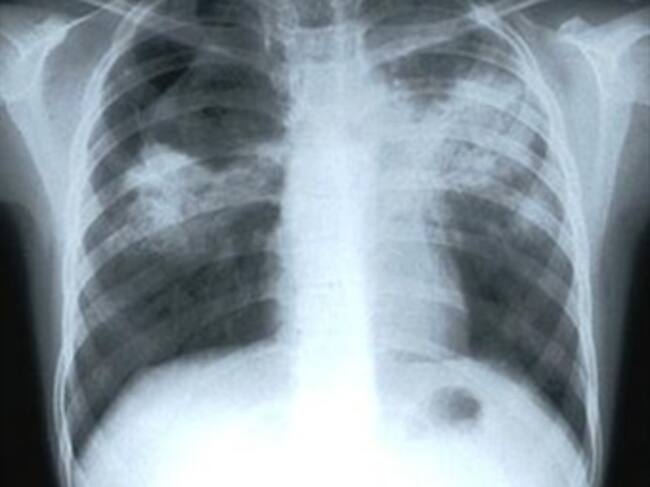

El brote de tuberculosis que causó la muerte de dos internos y el traslado de urgencia de otros cinco al Hospital General de Barranquilla, es resultado de la falta de atención oportuna por parte de la EPS Caprecom, responsable de la salud de los reclusos en la cárcel Modelo, así lo afirmó el personero del distrito Jaime Sanjuan

Por su parte, La Secretaria de salud, Alma Solano solicitó a la Superintendencia realizar una investigación, porque los casos ya habían sido diagnosticados por la entidad de manera oportuna pero la EPS no tomó medidas de prevención para evitar la muerte de los internos

La Personería luego de una visita al penal y constatar las condiciones de hacinamiento abrió una investigación porque los internos no cuentan con garantías en sus derechos de salud